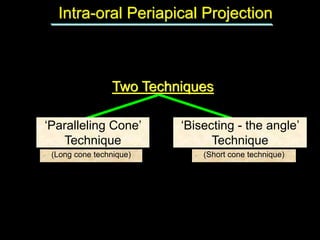

1. The document discusses various intra-oral radiographic techniques including the paralleling cone technique and bisecting angle technique.

2. The paralleling cone technique provides accurate images with little magnification and no superimposition but is more difficult for patients. The bisecting angle technique is easier for patients but results in more image distortion.